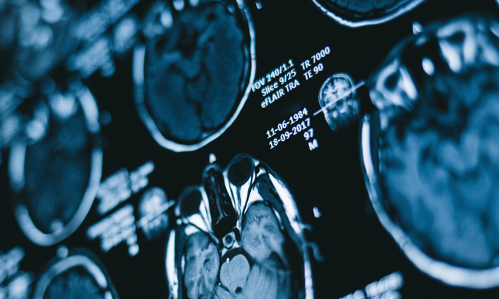

The Brain & Behavior Research Foundation is a global nonprofit organization focused on improving the understanding, prevention and treatment of psychiatric and mental illnesses.

Beginning in 1987, the Brain & Behavior Research Foundation was providing seed money to neuroscientists to invest in “out of the box” research that the government and other sources were unwilling to fund. Today, Brain & Behavior Research Foundation is still the leading, private philanthropy in the world in this space.